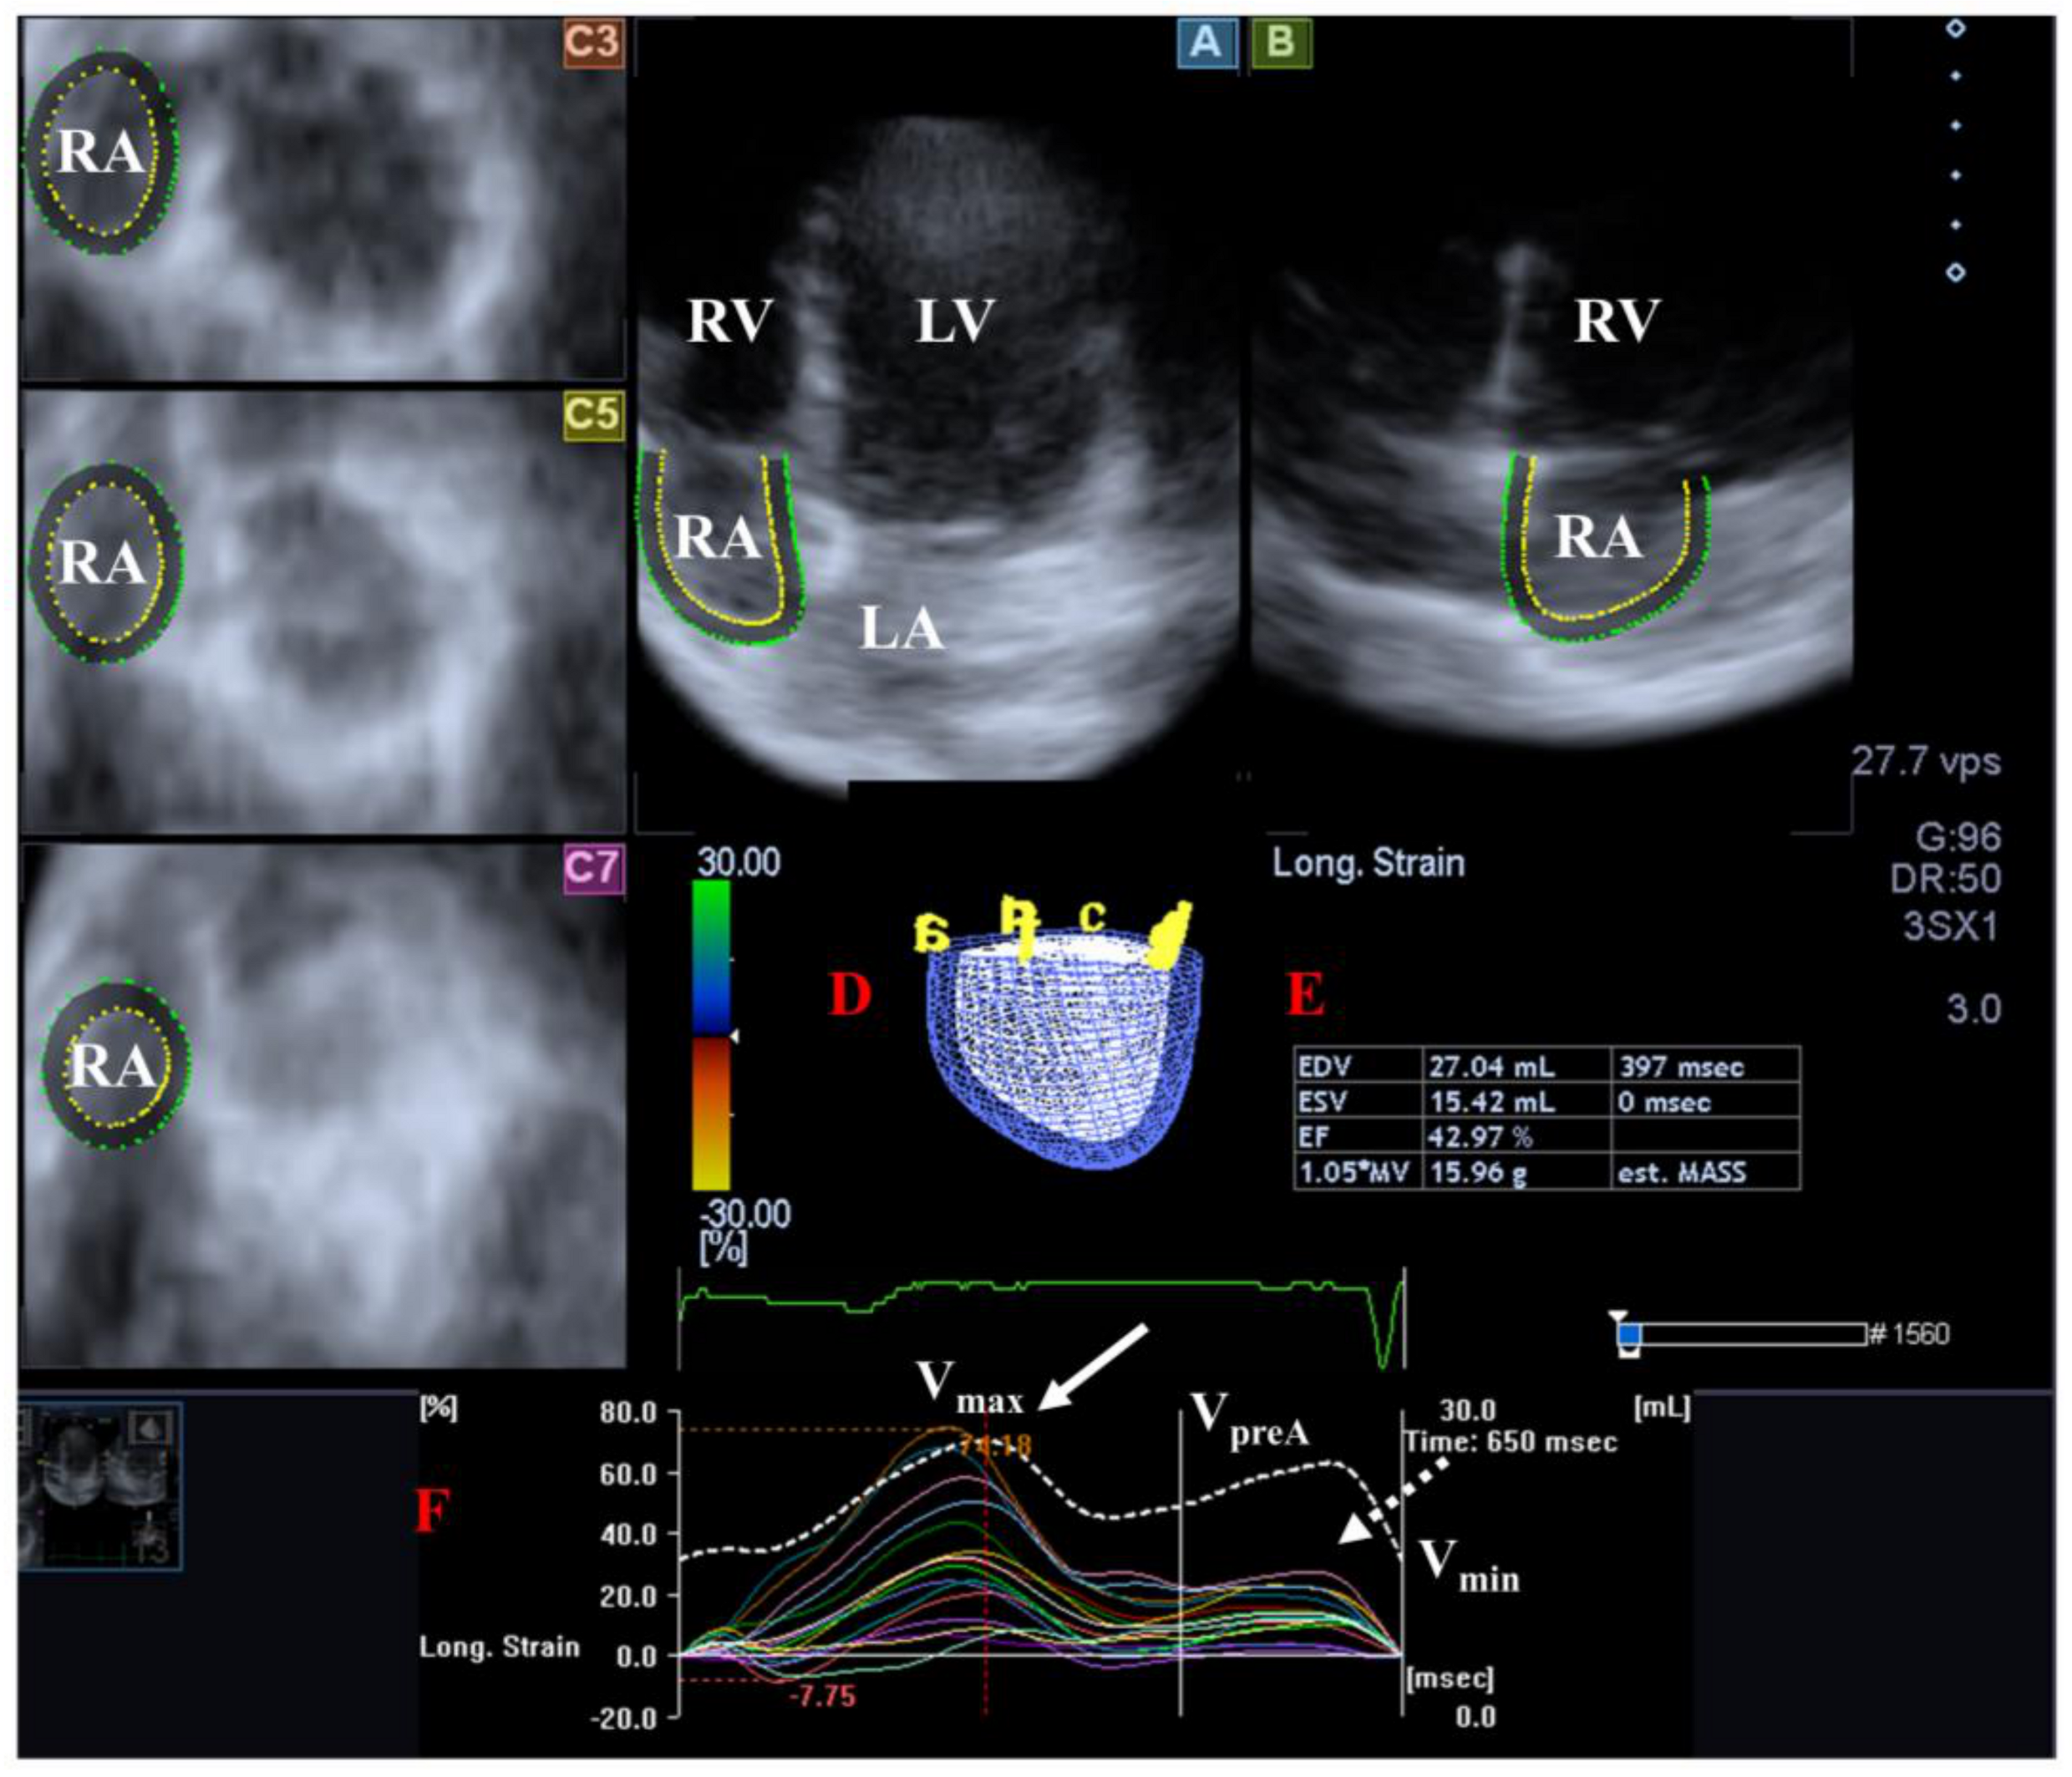

Figure 4.

Examination of the right atrium (RA) by three-dimensional (3D) speckle-tracking echocardiography. Following echocardiographic data acquisitions, the following typical views are created: (A) Apical 4-chamber and (B) two-chamber longitudinal views and (C3,C5,C7) cross-sectional views at basal, midatrial and superior levels, respectively. RA can be easily detected alongside other heart cavities including the left ventricle (LV) and atrium (LA) and the right ventricle (RV). A number of other details were also presented including (D) 3D cast and (E,F) maximum (Vmax), preatrial contraction (VpreA) and minimum (Vmin) volumes of the RA and curves representing changes in volumes and strains of _RA over time. Reservoir (peak) and active contraction RA strains are represented by white and dashed white arrows, respectively.